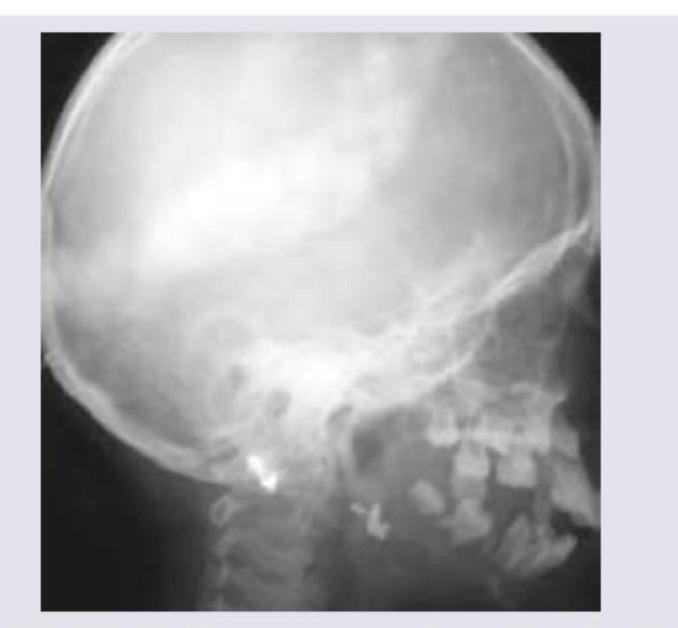

Explanation: **_Silver-beaten skull_** - The image displays a "beaten copper" or "silver-beaten" appearance of the skull, characterized by diffuse **lucencies and sclerotic changes** that resemble gyri and sulci impressions due to increased intracranial pressure. - This finding is often associated with conditions causing **chronic increased intracranial pressure** in children with open sutures. *Multiple myeloma* - Multiple myeloma typically presents with widespread, discrete, well-defined **lytic lesions** ("punched-out" lesions) in the skull, unlike the diffuse impression pattern seen here. - It is a plasma cell malignancy and usually affects older adults. *Histiocytosis-X* - Histiocytosis-X (now Langerhans cell histiocytosis) can cause lytic skull lesions, which are usually solitary or multiple, but often have a characteristic **beveled edge** or "hole within a hole" appearance, not the diffuse gyral impressions. - These lesions are typically more destructive and erosive. *Hydrocephalus* - While hydrocephalus causes increased intracranial pressure, leading to the "silver-beaten" appearance in children, hydrocephalus itself refers to the **accumulation of CSF**. - The "silver-beaten skull" is a radiological sign of chronic increased intracranial pressure, rather than the diagnosis of hydrocephalus itself, which is the underlying cause.